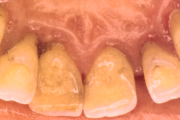

- igemepiir on taandunud (3)

- hamba kinnitussidemete kadu (3)

- puudulik suuhügieen (5)

- igemepealne hambakivi (5)

- igemealune hambakivi (4)

- vahed hammaste vahel (5)

- hammaste tundlikkus (9)